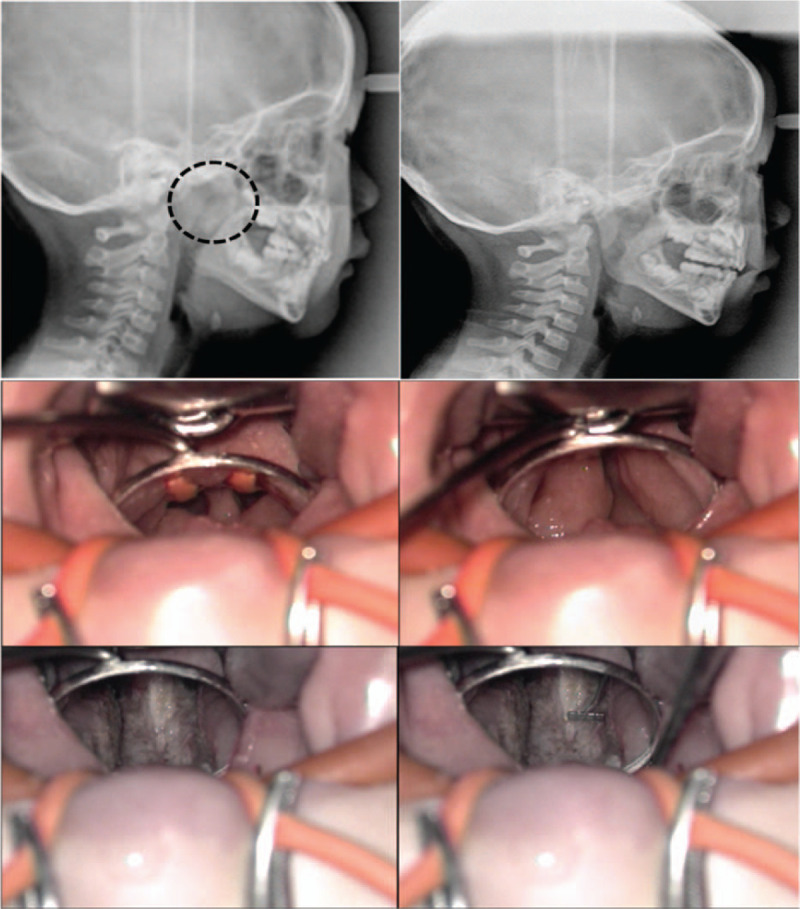

The 7 children were all boys with a median age of 5.0 years (first quartile 3.0, third quartile 12.0). The median age at the time of the first operation was 3.0 years (first quartile 2.0, third quartile 3.0) and the average time interval between the first operation and subsequent partial resection of TTH in our clinic was 44.0 (range 11–100) months (Table 1). All patients had a history of recurrent middle ear effusion. The nasopharyngeal airway space was confirmed to be narrowed in all patients on simple lateral cephalometry. Computed tomography showed bilateral enlargement of the torus tubarius area (Fig. 1). Intraoperatively, residual or recurrent adenoid tissues were minimal. The average preoperative width between the right and left torus tubarius was 2.1 (range, 1–3) mm. The width between the right torus tubarius and the left torus tubarius was enlarged to 8 mm (Fig. 2).

Figure 2.

Preoperative and postoperative cephalometry (top). Intraoperatively findings shows narrowing of the airway space between hypertrophic torus tubarius (2 mm in width) (middle). Postoperatively, nasopharyngeal width becomes 8 mm with a 4-mm measure (bottom).